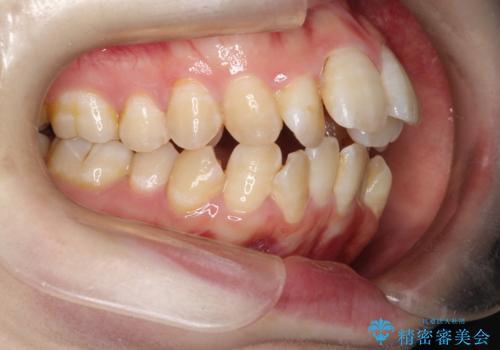

咬み合わせが気になる ワイヤー矯正による咬み合わせ改善と奥歯のセラミック治療

重度のガタガタ ワイヤーによる抜歯矯正